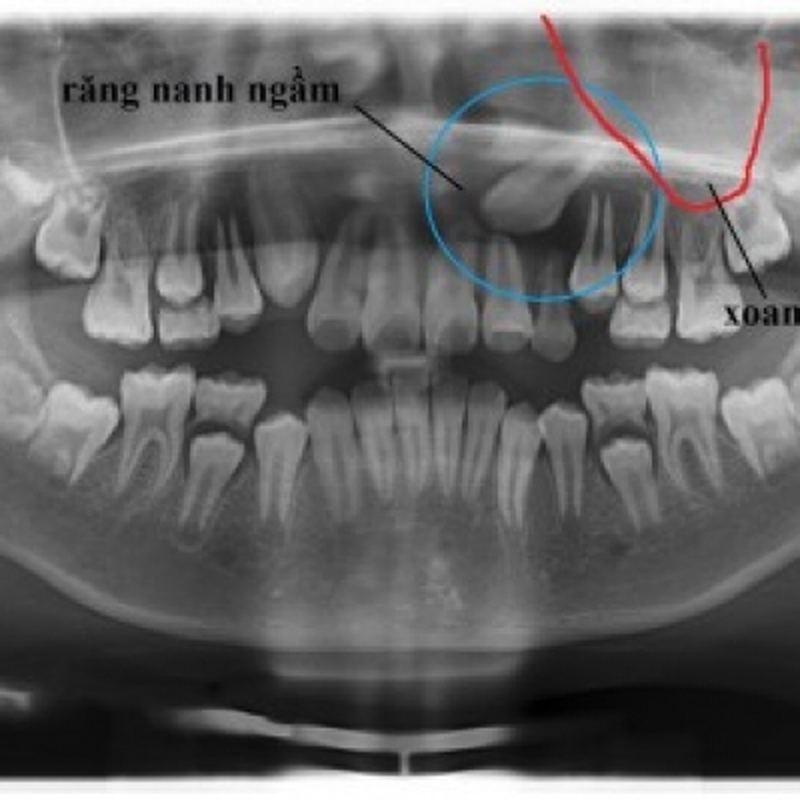

Răng mọc ngầm là răng mọc nằm sâu bên trong xương hàm hoặc ngay dưới nướu nhưng không thể tách nướu ra và trồi lên trên được. Những chiếc răng mọc ngầm hoàn toàn có thể mọc đầy đủ nguyên vẹn như những răng bình thường khác hoặc cũng có thể chỉ ở dạng nang.

Nguy cơ răng mọc ngầm có thể xảy ra ở mọi răng vĩnh viễn, trong đó hay gặp nhất là răng khôn. Bởi vì răng này thường mọc muộn nên thiếu khoảng trống cho răng trồi lên. Kế đến là các răng nanh hàm trên, răng hàm nhỏ của hàm dưới và răng cửa giữa của hàm trên cũng thường có răng mọc ngầm.

/https://cms-prod.s3-sgn09.fptcloud.com/rang_moc_ngam_co_nen_nho_hay_khong_1_48c1e04160.jpg) Răng mọc ngầm là răng mọc nằm sâu bên trong xương hàm hoặc ngay dưới nướu nhưng không thể tách nướu ra và trồi lên trên được

Răng mọc ngầm là răng mọc nằm sâu bên trong xương hàm hoặc ngay dưới nướu nhưng không thể tách nướu ra và trồi lên trên đượcRăng mọc ngầm là một trong những nguyên nhân gây ảnh hưởng tới sức khỏe răng miệng và tính thẩm mỹ của khuôn mặt với các răng mọc ngầm ở hàm dưới và các răng mọc ngầm hàm trên. Không những vậy, các răng mọc ngầm còn làm tăng nguy cơ bệnh lý nhiễm trùng răng miệng, phá hủy các răng bình thường bên cạnh hoặc tổn thương dây thần kinh.